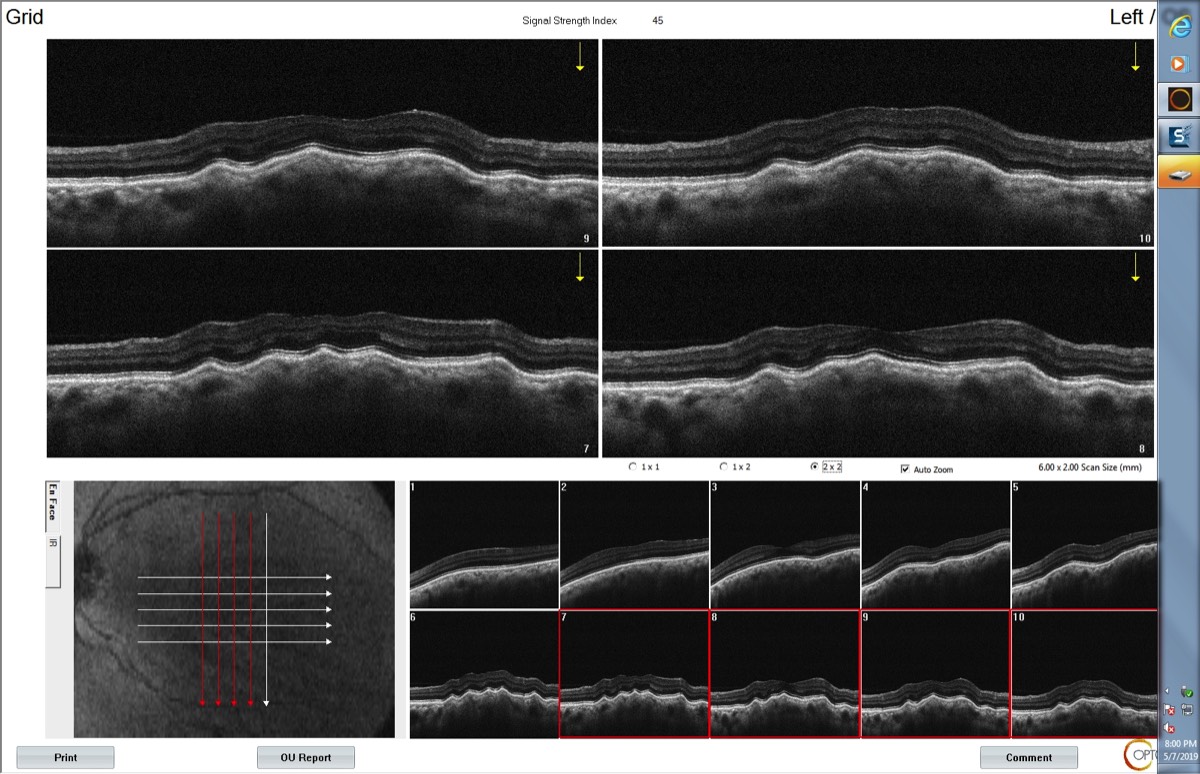

Chorioretinal folds (posterior scleritis) by Eidon (CenterVue- Italy)

Plis chorio-rétiniens (sclérite postérieure)

OCT: